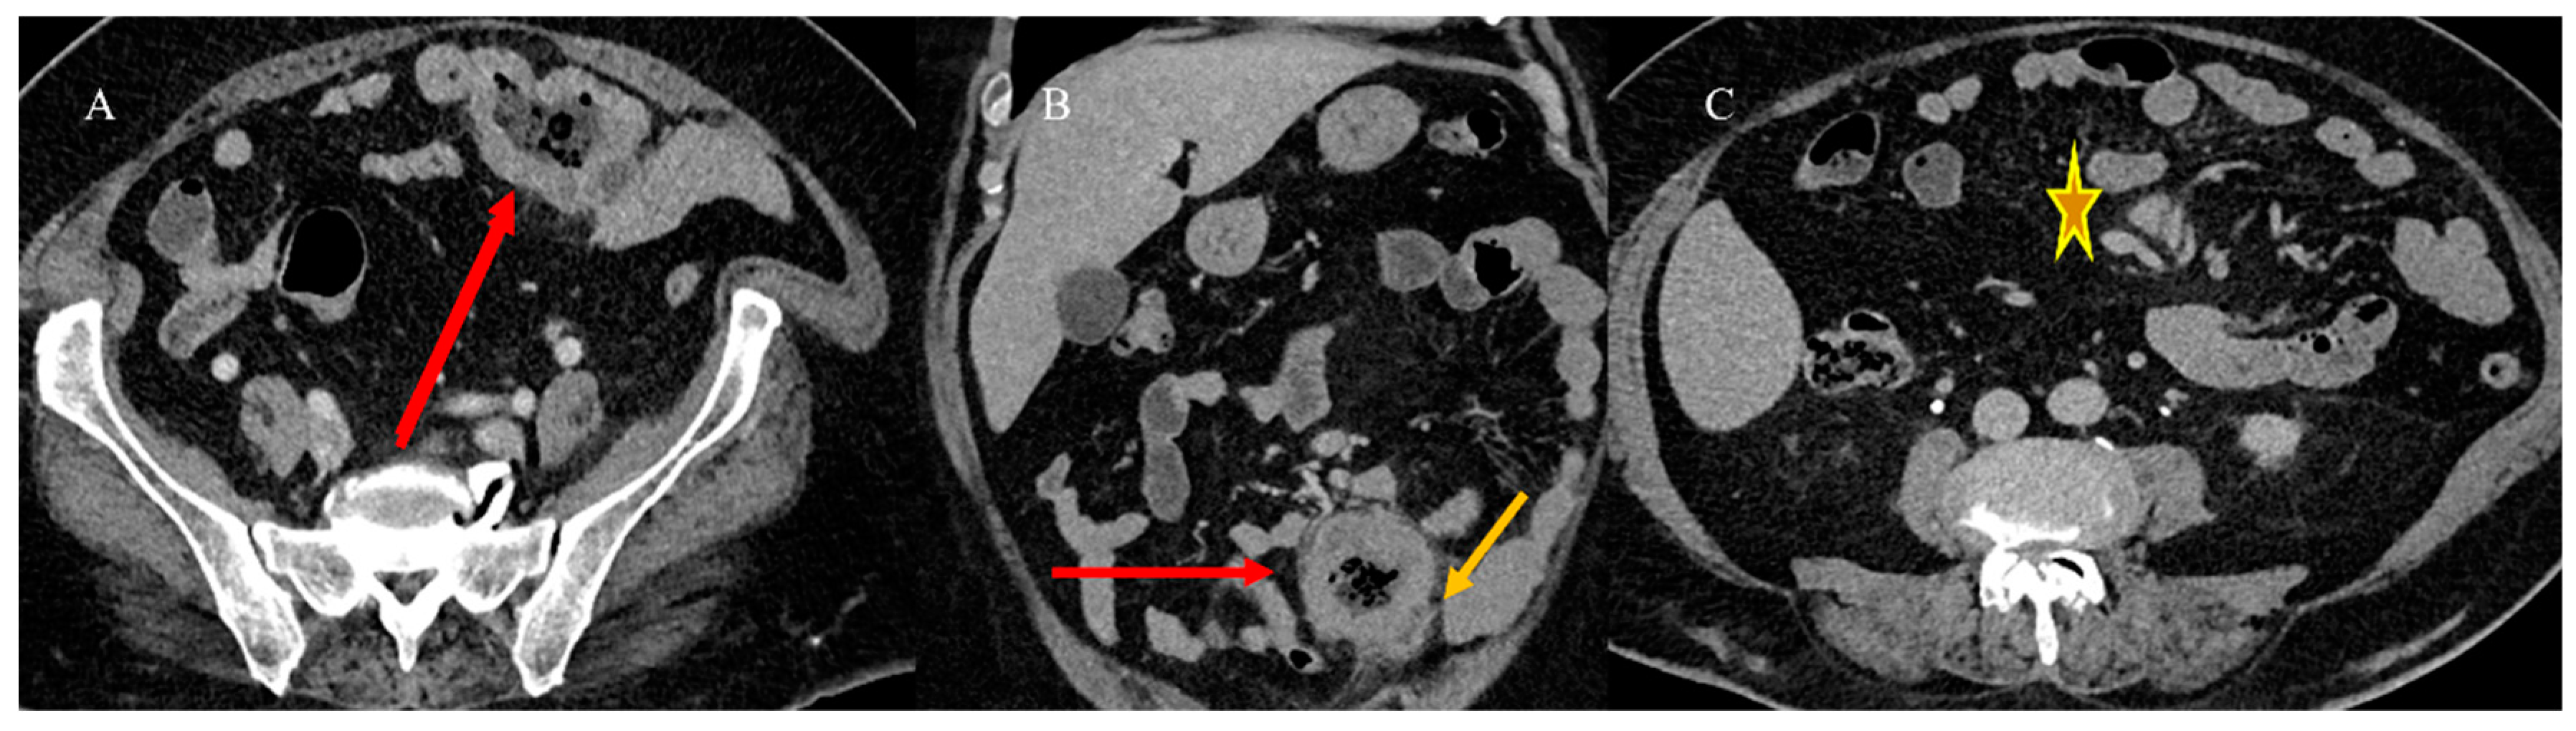

- Tuca, A.; Guell, E.; Martinez-Losada, E.; Codorniu, N. Malignant bowel obstruction in advanced cancer patients: Epidemiology, management, and factors influencing spontaneous resolution. Cancer Manag. Res. 2012, 4, 159–169. [Google Scholar] [CrossRef]

- Alshamsan, B.; Aseafan, M.; Badran, A.; Shaheen, A.; Elshenawy, M.A.; Bazarbashi, S.; Aljubran, A.H. Characteristics and outcomes of small bowel adenocarcinoma: 14 years of experience at a single tertiary hospital in Saudi Arabia. Mol. Clin. Oncol. 2023, 18, 17. [Google Scholar] [CrossRef]

- Kroepfl, V.; Bellotti, R.; Gasser, E.; Esswein, K.; Esser, H.; Kafka-Ritsch, R.; Öfner, D.; Perathoner, A. Small bowel neuroendocrine tumors: An analysis of clinical presentation, diagnostic workup and surgical approach—A single center retrospective study. Front. Surg. 2023, 10, 1072435. [Google Scholar] [CrossRef]

- Basendowah, M.H.; Ashour, M.A.; Hassan, A.Y.; Alshaynawi, S.; Alyazidi, L.K. Multiple small intestinal neuroendocrine tumors with findings of intestinal obstruction. Cureus 2021, 13, e17629. [Google Scholar] [CrossRef] [PubMed]

- Behi, H.; Omry, A.; Dallagi, R.; Changuel, A.; Troudi, D.; Khalifa, M.B. Diagnosing and managing small bowel neuroendocrine tumors presenting as acute obstruction in an elderly patient: A case report and comprehensive management overview. Int. J. Surg. Case Rep. 2024, 122, 110126. [Google Scholar] [CrossRef]

- Nelms, D.W.; Kann, B.R. Imaging modalities for evaluation of intestinal obstruction. Clin. Colon. Rectal Surg. 2021, 34, 205–218. [Google Scholar] [CrossRef]

- Paulson, E.K.; Thompson, W.M. Review of small-bowel obstruction: The diagnosis and when to worry. Radiology 2015, 275, 332–342. [Google Scholar] [CrossRef] [PubMed]